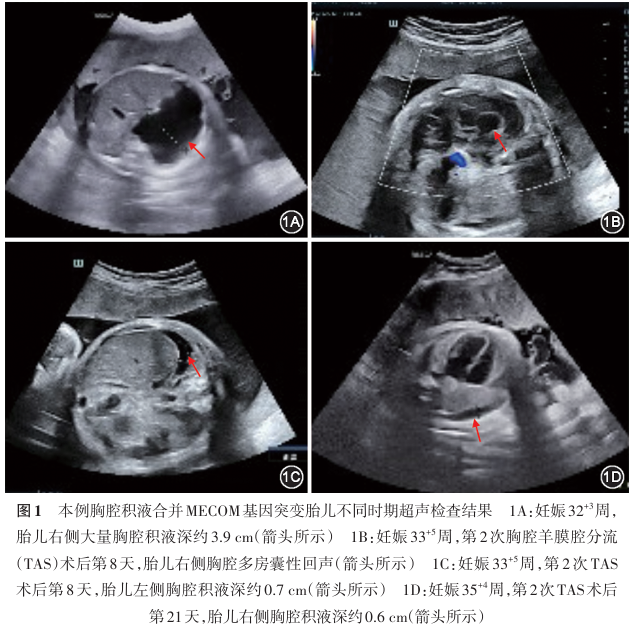

本文报道1例妊娠晚期发现的胎儿胸腔积液合并MECOM基因突变最终致新生儿先天性尺桡骨融合伴无巨核细胞性血小板减少。孕妇因“停经29 +6周,发现胎儿右侧胸腔积液半天”入院。胎儿胸腔穿刺结果提示原发性胸腔积液,因胸腔积液反复增加,先后2次行胎儿右侧胸腔羊膜腔分流术。第2次分流术后出现右侧胸腔多房囊性回声,予观察。妊娠35 +5周因胎膜早破、瘢痕子宫不规律宫缩行剖宫产术。新生儿出生后因胸腔积液行胸腔穿刺及胸腔闭式引流,血常规提示血小板少,伴左侧尺桡骨融合,家系全外显子组测序确诊MECOM基因突变致尺桡骨融合伴先天性无巨核细胞性血小板减少。胎儿胸腔积液罕见,胸腔穿刺后出现胸腔多房囊性回声应考虑胎儿血小板减少可能,产后多学科团队协作有利于该病的诊疗,家系全外显子组测序分析有利于进一步明确诊断。

据文献报道,目前尚未将MECOM基因纳入胎儿水肿的目标基因 [ 17 , 18 ] ,也尚无MECOM基因突变引起FHT并行宫内治疗的报道。本例第2次TAS后出现右侧胸腔囊性分隔,考虑不排除局部感染、出血;患儿出生后血常规检查提示血小板极低,初步考虑与血小板少的胸腔局部出血有关。文献报道的3例胎儿 [ 16 , 17 ] 均出现了水肿,出生后进一步检查提示严重贫血,本例胎儿MCA-PSV检查未见异常,胸腔穿刺液常规检查提示淋巴细胞为99%,与原发性胸腔积液相符,出生后血常规检查未提示贫血,故本例是否为原发性胸腔积液合并MECOM基因突变,期待积累更多的病例进一步研究。